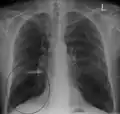

A chest X-ray is not useful to establish a diagnosis of COPD, but it is of use in either excluding other conditions or including comorbidities such as pulmonary fibrosis and bronchiectasis. Characteristic signs of COPD on X-ray include hyperinflation (shown by a flattened diaphragm and an increased retrosternal air space) and lung hyperlucency.[5] A saber-sheath trachea may also be shown that is indicative of COPD.[111]

Chest X-ray demonstrating severe COPD, displaying small heart size in comparison to the lungs